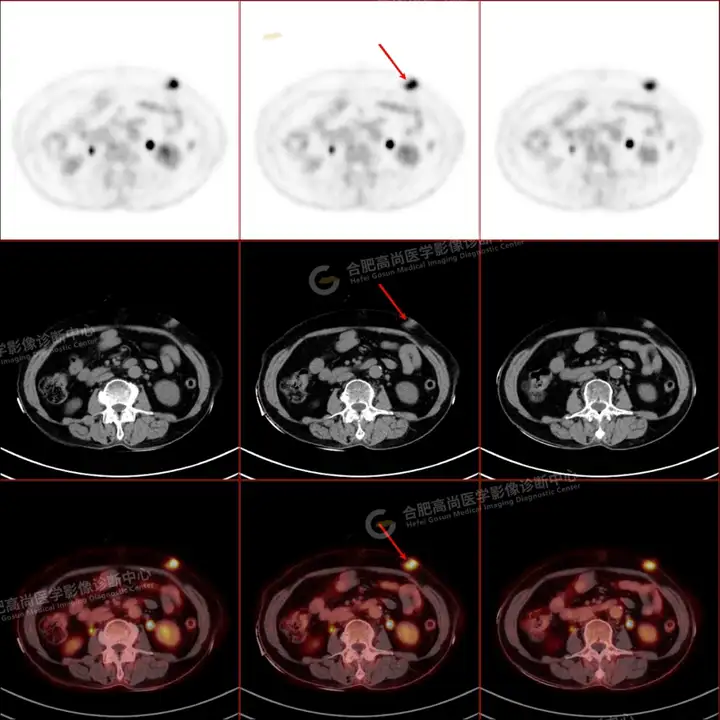

PETCT检查所示:图1、3-17全身多处(双上臂、胸背部、左侧乳腺、左侧腰部、腹壁、双侧臀部及双侧大腿)皮肤下结节及肿块样软组织密度灶,FDG代谢不同程度增高,双侧颈部、左侧锁骨区、纵隔内(1区)及双侧腋窝多发肿大淋巴结,FDG代谢明显增高,符合皮肤来源淋巴瘤。